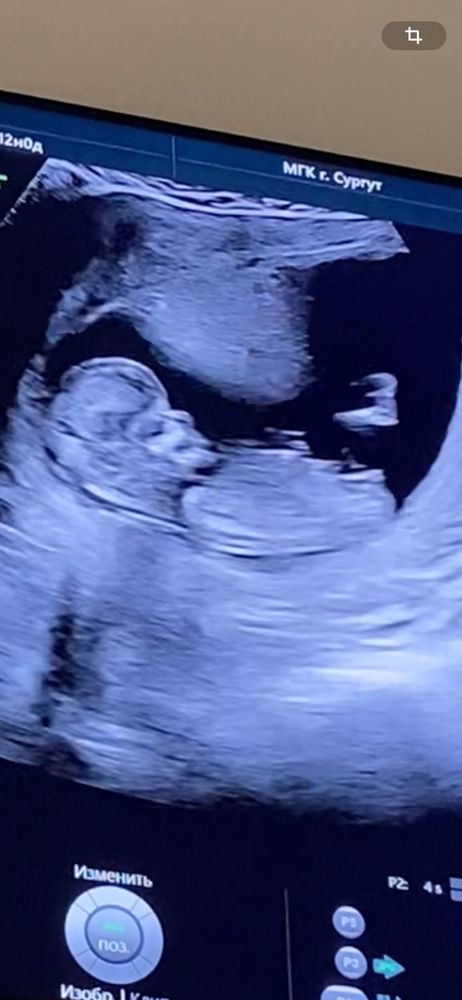

Здравствуйте! Кто нибудь может по половому бугорку определить пол ребенка? Распирает уж очень от любопытства. Я на 1 скрининге предположила пол ребенка и врач со мной согласилась, хотя до этого сказала что пол невозможно определить.